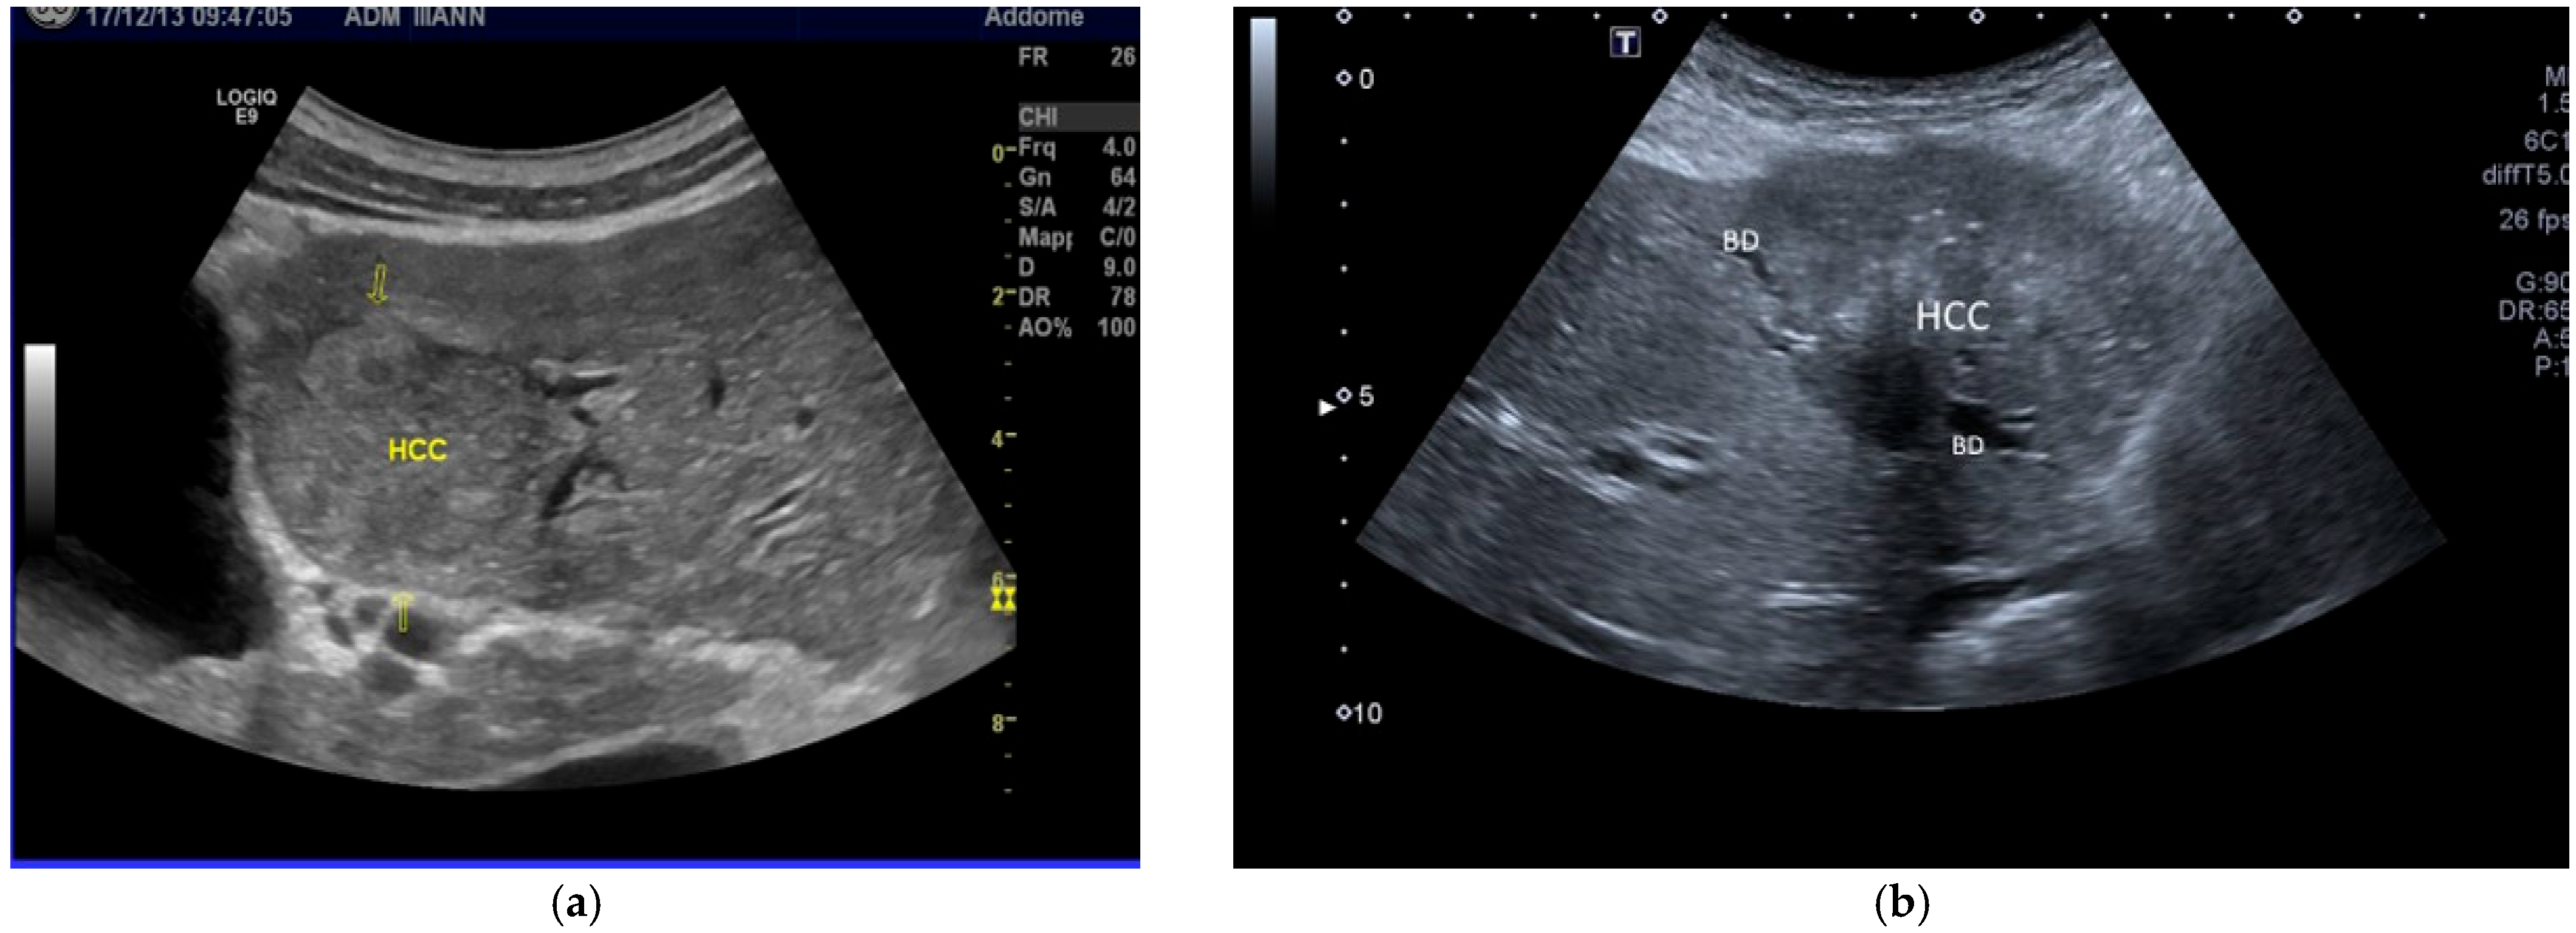

| POST-VIRAL HCC | MASLD HCC |

|---|---|

|

| |

| These characteristics would be focused more on the lack of malignancy rather than HCC. | |